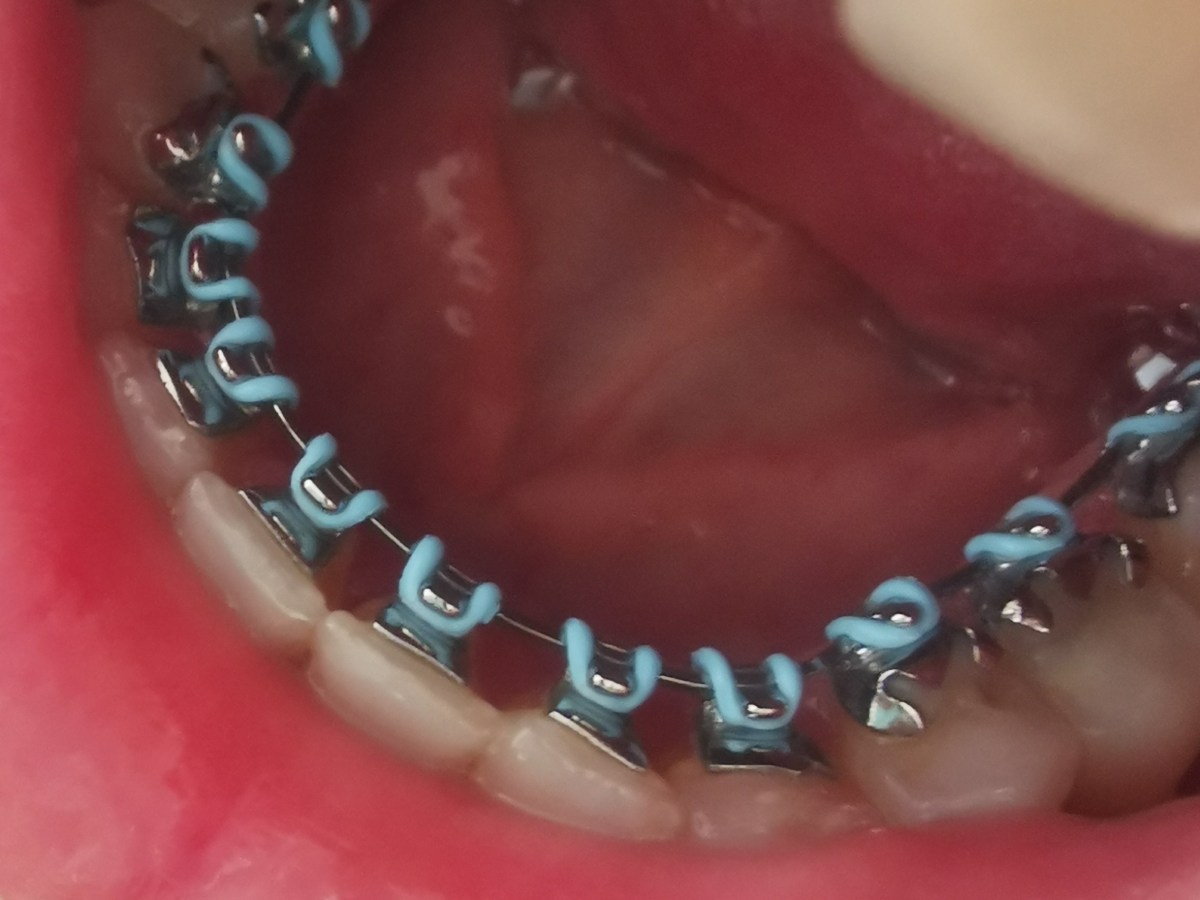

Anticoagulantele orale și intervențiile stomatologice

(Acest articol este viziunea mea în urma celor studiate și nu înlocuiește sfatul medical la cabinet, particularizat fiecărui caz. Va rog, luați legătura…

Mecanoproteza = dozare INR

Pentru ca întâlnesc tot mai mulți pacienți cu proteze cardiace, țin sa menționez aici 2 aspecte importante pentru ei: Imaginea atasata este preluata…